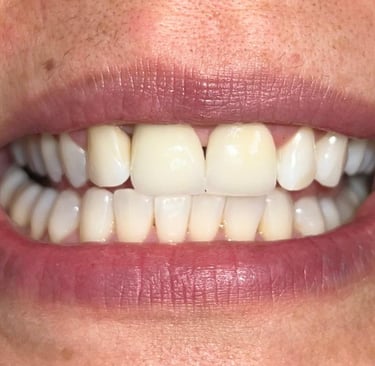

Coroas em Dissilicato de Lítio

Todos os caso a seguir estão associadas a clareamento dentário

Antes

Depois